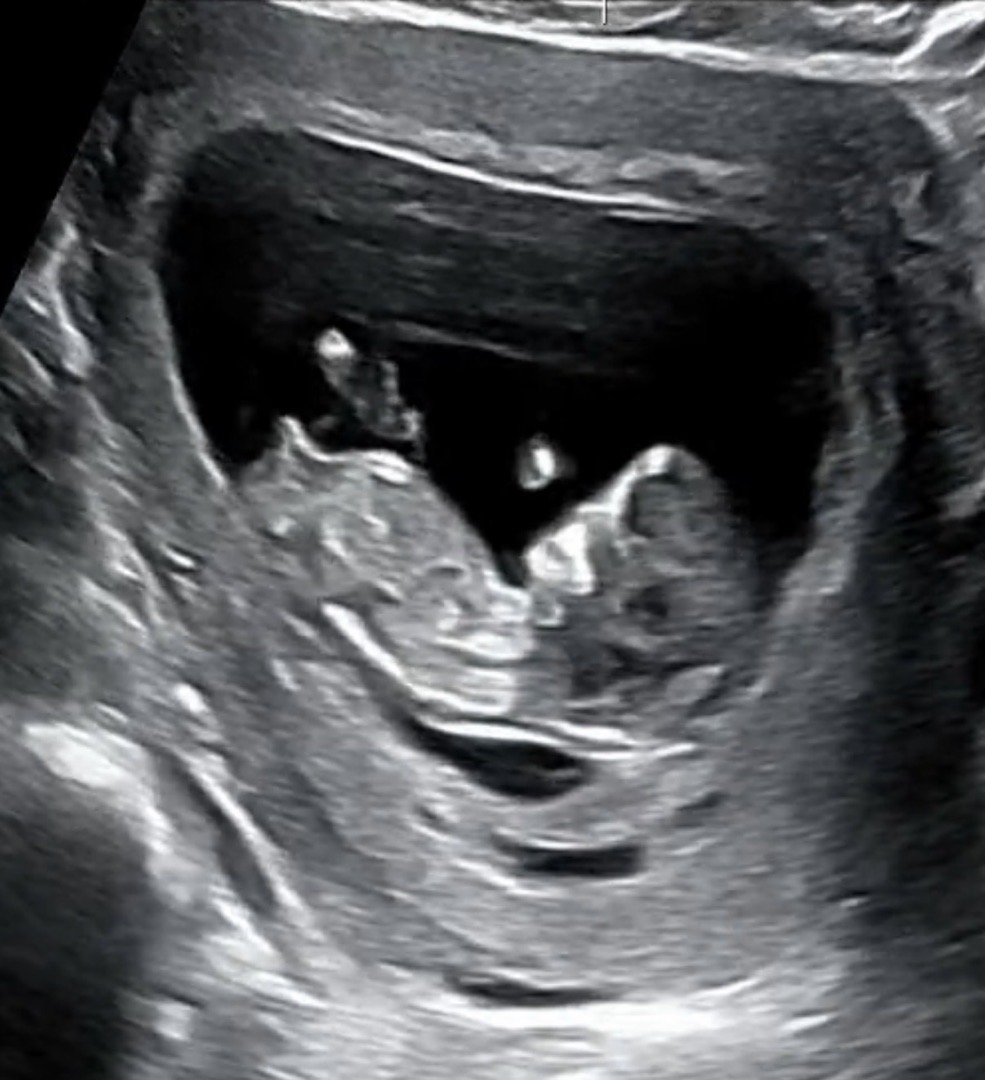

12주차 각도법 투표부탁드립니당!!!!!

아들일까요 딸일까용 ?